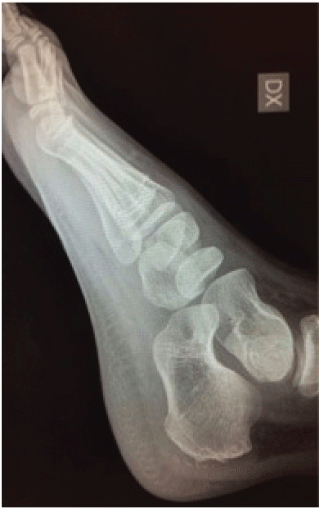

.

Figure 3: X-ray lateral view at first examination (Higher arrows: osteochondrosis of the medial cuneiform; Lower arrows: osteochondrosis of tarsal scaphoid).

View Figure 3